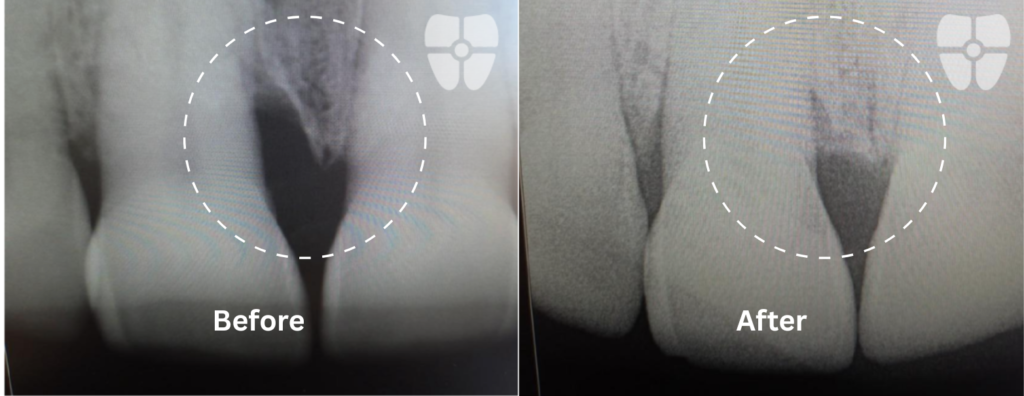

Non-Surgical Flapless Graft using Biological Materials and Periodontal Endoscopic Therapy:

The Results - 9 Months Apart

Real patient results achieved non-surgically with periodontal endoscopic therapy and biologics.

Decrease pocket depth, increase health. Proven to provide 40% less bleeding on probing than traditional periodontal therapies.